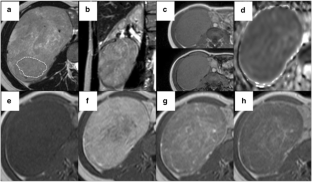

Fig. 3